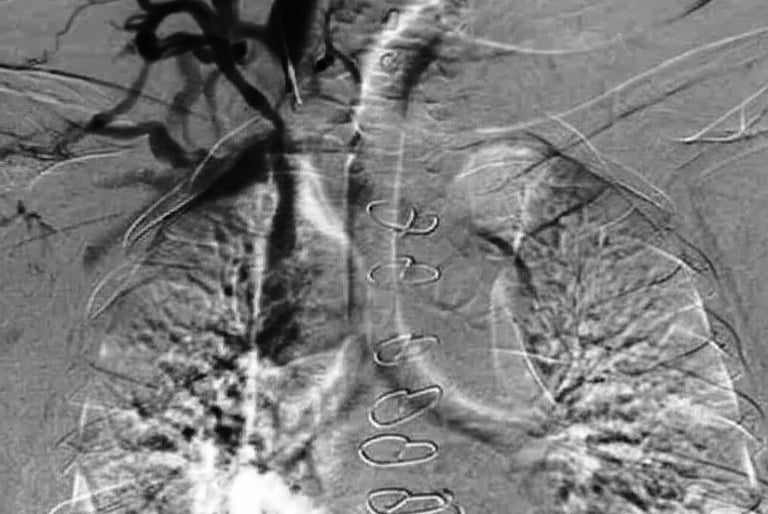

Flebografía de la vena ácigos en presencia de estenosis cavoatrial

Estenosis de la vena yugular con dilatación de sus efluentes